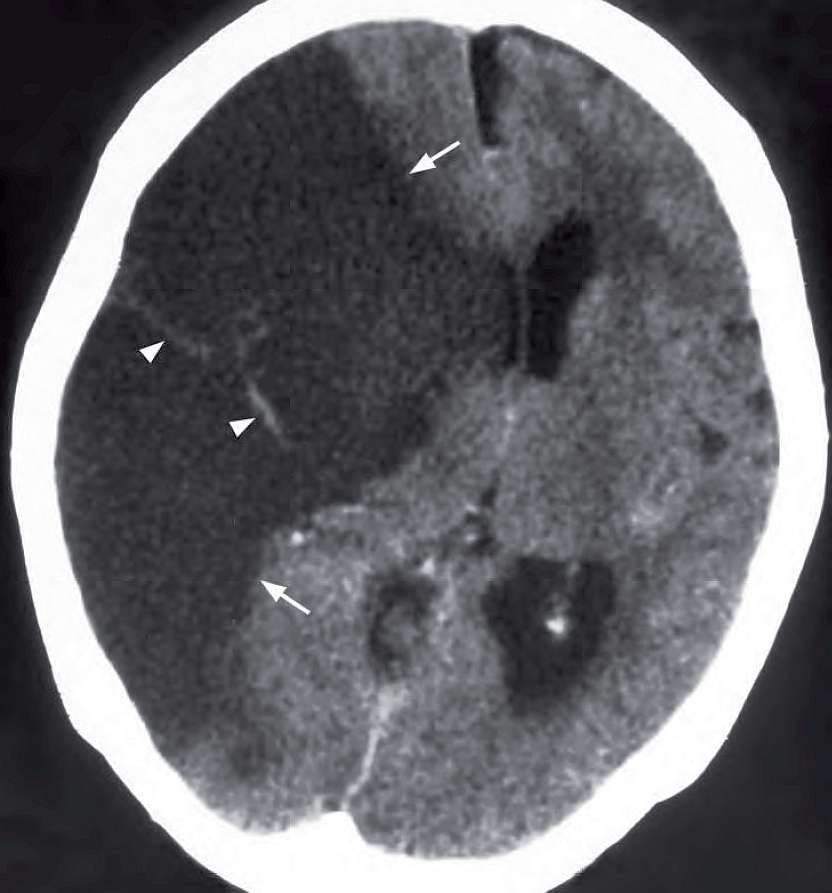

72-year-old woman with a history of poorly controlled hyperlipidaemia, hypertension and diabetes mellitus suddenly lost consciousness and developed left-sided weakness. Physical examination showed a BP of 210/120 mmHg. An urgent CT brain was performed.

What is seen on the CT and what is the diagnosis ?